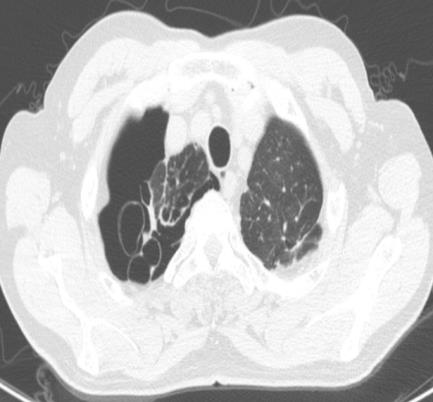

• 右肺中叶病变的临床特征分析(附709例报告)

2026, 32(3):45-50. DOI: 10.12235/E20250294

摘要 (42) HTML (59) PDF 1.50 M (41) 评论 (0) 收藏

摘要:目的 探讨右肺中叶支气管异常患者的人口学特征、临床表现、病因、影像学表现和支气管镜下表现。方法 回顾性分析2015年5月-2025年4月于该院在支气管镜检查中表现为右肺中叶异常改变的709例患者的临床资料,统计分析病因和临床特征。结果 709例患者中,男465例,女244例。男患者年龄(63.1±9.1)岁,明显高于女患者的年龄(60.9±11.5)岁,差异有统计学意义(P < 0.05)。临床表现主要包括:咳嗽、气促、咯血、痰中带血和胸痛,9.9%的患者未出现临床症状。根据年龄范围进行分组,将年龄 > 55岁的542例(76.4%)患者纳入高龄组,≤55岁的167例(23.6%)患者纳入低龄组,高龄患者明显多于低龄患者,差异有统计学意义(P < 0.05)。高龄组中,常见的3种病因分别为:肿瘤、炎症和结核。支气管镜下表现为:右中叶新生物、黏膜肥厚或肿胀、管腔狭窄和瘢痕闭塞等。结论 右肺中叶病变的患者采用影像学和支气管镜相结合的方式,对明确病因和指导临床治疗有重要意义。